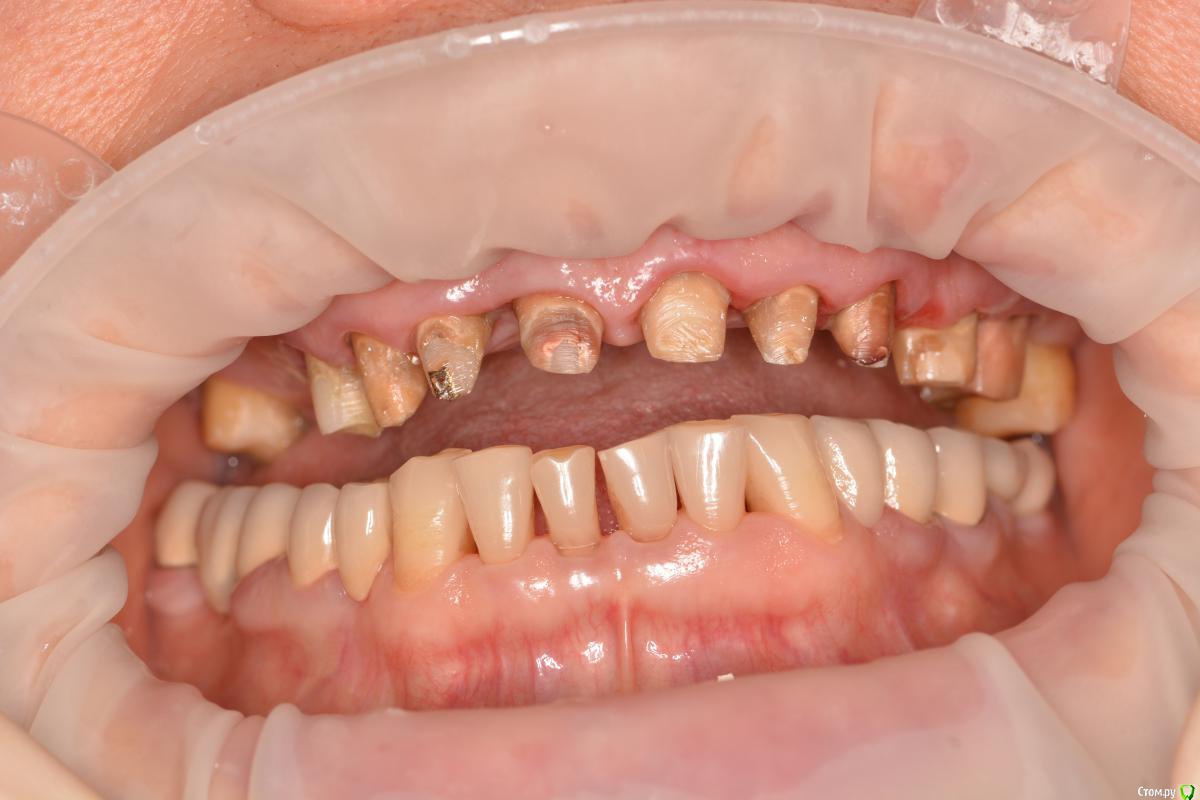

Alexandr1984 Опубликовано 29 марта, 2016 Поделиться Опубликовано 29 марта, 2016 Коллеги, что можно здесь сделать? Речь о верхней челюсти.Пациент родственник. Хотелось бы добиться наилучшей эстетики, особенно во фронте. Ранее стоял металлокерамический мост (подкова). более 15 лет. Можно ли протезировать одиночками?Мысль такая: зубы были шинированы мостом, возможно связочный аппарат частично атрофировался. Не появится ли подвижность при протезировании одиночными коронками? В 1-м сегменте планируется имплантация с синусом. Применим ли имакс к этим зубам? если да, то как фиксировать под десной по адгезивному протоколу? И что делать с темным цветом культей? заранее спасибо) Ссылка на комментарий

Alexandr1984 Опубликовано 29 марта, 2016 Автор Поделиться Опубликовано 29 марта, 2016 Коллеги, и что бы вы сделали с провалом десны между 11 и 12 зубами? там глубокий карман, который после протезирования будет давать визуальный дефект! Ссылка на комментарий

Карен Аванесов Опубликовано 30 марта, 2016 Поделиться Опубликовано 30 марта, 2016 С такой местами конусностью и низкой высотой культей, плюс подсыревшим местами дентином, и передавленным местами подковой пародонтом, с надежной фиксацией единичек и здоровьем пародонта будут проблемы. Все делается в комплексе. и еще как вы пресс с коффером то при такой ситуации будете фиксировать? Ссылка на комментарий